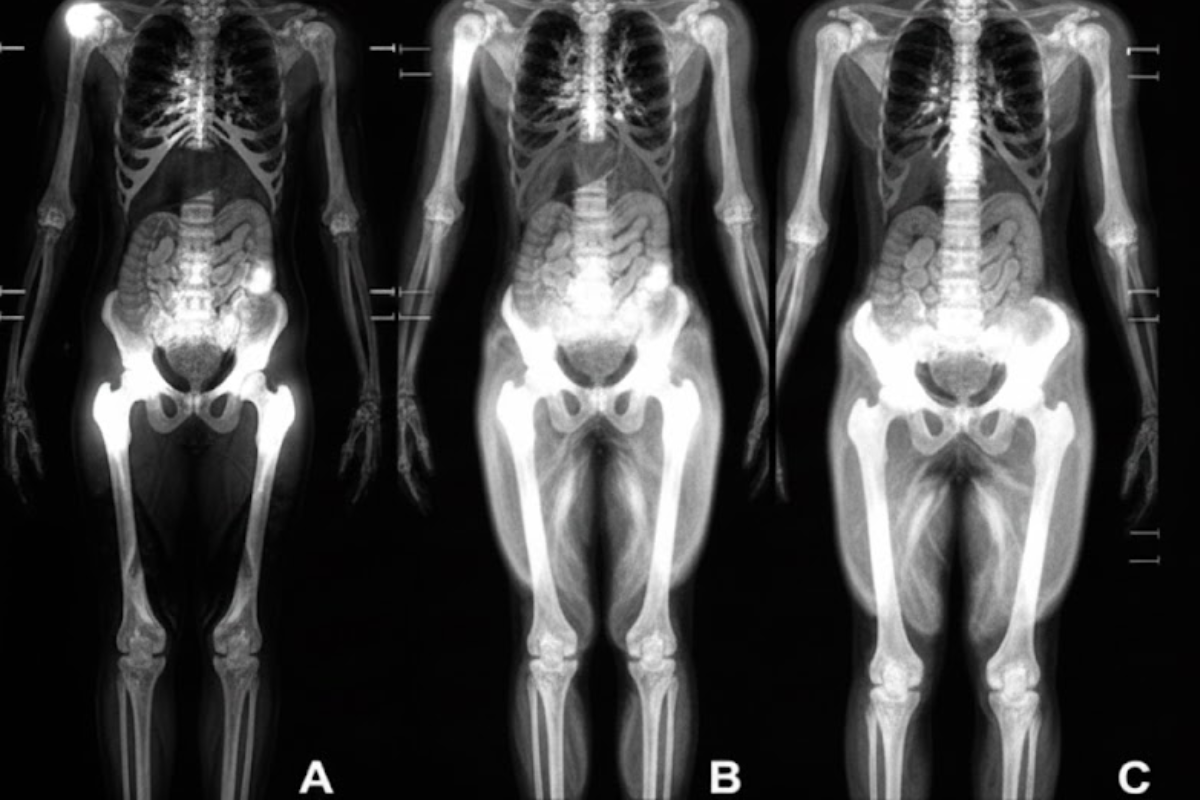

Nghiên cứu thực hiện trên 1.164 người trưởng thành khỏe mạnh (52% là nữ) tại bốn địa điểm bằng phương pháp chụp MRI toàn thân. Những người tham gia có độ tuổi trung bình theo thời gian là 55,17 tuổi. Hình ảnh chụp bao gồm các chuỗi MRI có trọng số T1, làm nổi bật mỡ sáng và mỡ lỏng cũng như mỡ tối, mang lại hình ảnh rõ nét về cơ, mỡ và mô não. Sau đó, người ta sử dụng một thuật toán trí tuệ nhân tạo (AI) để đo tổng thể tích cơ chuẩn hóa, mỡ nội tạng (mỡ bụng ẩn), mỡ dưới da (mỡ dưới da) và tuổi não dự đoán.

Hình ảnh minh họa cho ảnh chụp MRI trong việc nghiên cứu.